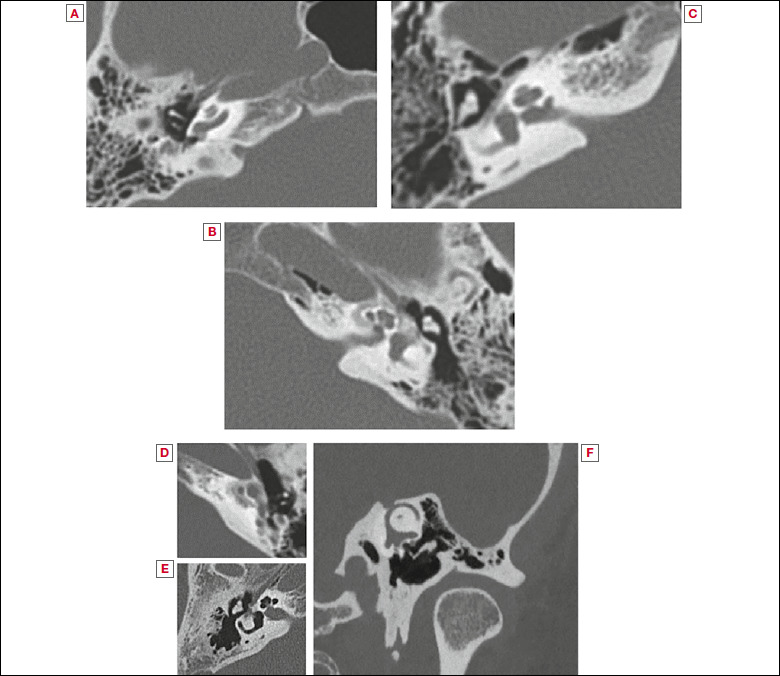

Abstract Image